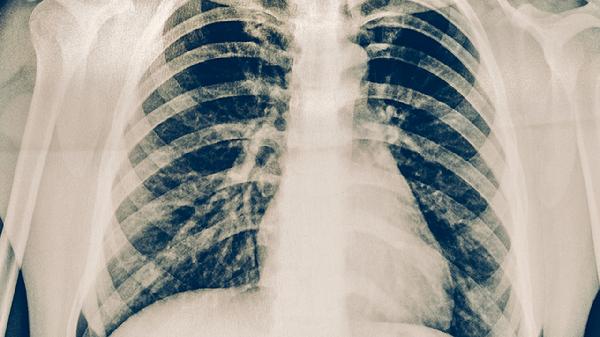

少数情况下转移肺癌可呈现非典型表现,如磨玻璃样结节多见于肺泡内转移的恶性肿瘤,常见于甲状腺癌或肾癌转移。混合性结节则可能出现在伴有出血或坏死的转移灶中,多见于绒毛膜癌等滋养细胞肿瘤转移。某些特殊类型转移瘤还可能形成空洞或钙化,如骨肉瘤肺转移可能出现钙化结节。

发现肺部结节应及时进行增强CT、PET-CT等检查评估特征,通过支气管镜或穿刺活检获取病理诊断。治疗需根据原发肿瘤类型制定个性化方案,可能涉及手术切除、放疗、靶向治疗或免疫治疗等多种手段。日常需避免吸烟及二手烟暴露,保持规律作息以维持免疫功能,出现持续咳嗽、胸痛等症状应立即复查。